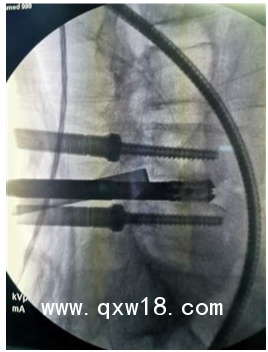

UBE技術(shù)即單側(cè)雙通道內(nèi)鏡技術(shù)(Unilateral Biportal Endoscopy Technique),適用于頸椎、胸椎、腰椎的退行性病變。與椎間孔鏡的單通道不同,該技術(shù)通常建立兩個通道,一個為觀察通道,一個為器械操作通道。觀察通道一般會用到0°或30°UBE內(nèi)鏡,操作通道使用UBE專器械,如UBE刮匙、磨鉆(UBE內(nèi)鏡磨頭)、UBE內(nèi)鏡刨刀、UBE內(nèi)鏡消融電極、UBE椎板咬骨鉗、UBE髓核鉗、UBE神經(jīng)拉鉤等。UBE技術(shù)的專用器械包,通過UBE技術(shù)還可以完成鏡下融合手術(shù)。

該技術(shù)開展脊柱手術(shù)時,克服了中心管狹窄、側(cè)管狹窄和椎間孔狹窄的局限。手術(shù)入路角度范圍廣,在不損傷脊柱結(jié)構(gòu)完整性的前提下,有效地對椎管進行了周向和局部減壓,保留了肌肉韌帶附著通過肌間間隙,保護背支內(nèi)側(cè)支,從而防止?fàn)繌垞p傷。這種內(nèi)窺鏡入路允許從對側(cè)后入路和孔外入路(椎旁孔外入路)進入孔,為治療所有類型的狹窄提供了靈活性,因此,UBE技術(shù)作為一種微創(chuàng)的融合方法,具有極強的實用性。

6、適應(yīng)癥廣泛,能輕松完成鏡下融合、頸椎、胸椎、腰椎等復(fù)雜病例。